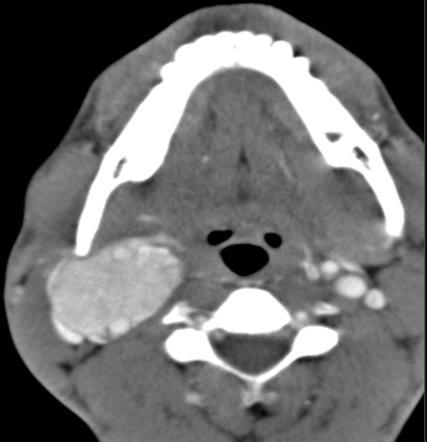

甲状舌骨囊肿?表皮样囊肿伴感染?

甲状舌骨囊肿